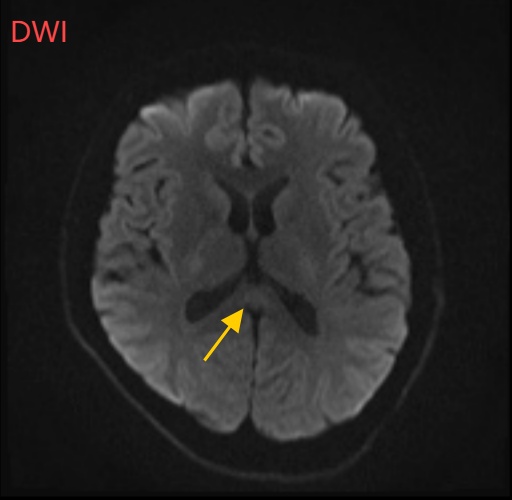

经过头部磁共振平扫、弥散、增强影像等检查

小董的影像结果显示,胼胝体压部发生病变

入院4天后,小董的不适感消失,神志完全恢复,讲话正常,没有幻觉和视物不清;

经过一周治疗,小董的胼胝体压部病变明显好转